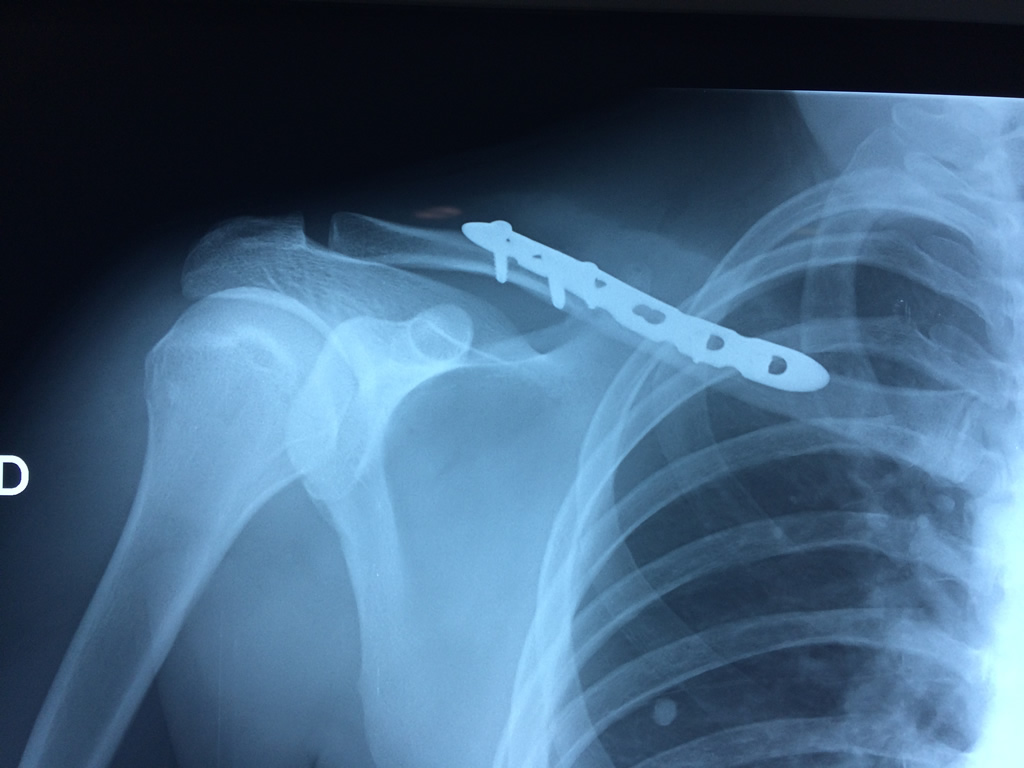

Cirugía de Fémur - Clavícula

La clavícula es un hueso largo, con forma de "S" itálica, situado en la parte anterosuperior del tórax. Junto con la escápula forman la cintura escapular. Se puede palpar por toda su longitud y se extiende del esternón al acromion de la escápula, siguiendo una dirección oblicua lateral y posterior.

Se considera el único medio de unión entre el miembro superior y el tórax. A pesar de su aspecto, similar al de un hueso largo, posee una estructura semejante a la de un hueso plano, ya que carece de epífisis y de diáfisis, lo que la harían entrar dentro de la clasificación de hueso largo. Carece de un canal medular propiamente dicho.